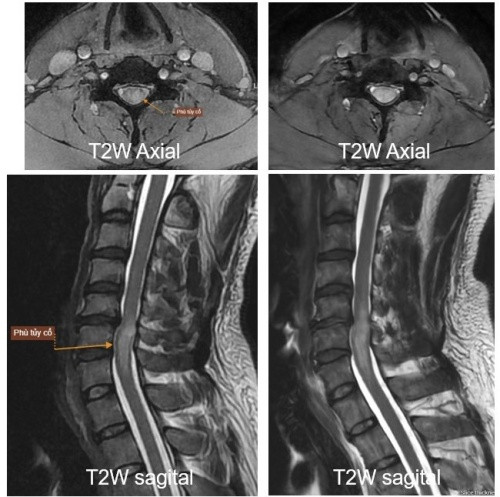

| Hình ảnh chẩn đoán qua chụp MRI tại Bệnh viện Mặt Trời |